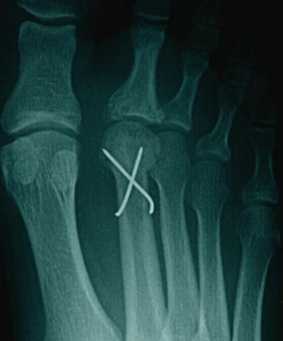

Используется 3 основных вида оперативных вмешательств: артротомия и дебридмент, дорсальная клиновидная остеотомия, частичная резекция головки плюсневой кости.

Артротомия и дебридмент в настоящее время применяется всё реже. Помимо удаления свободных хондромных тел, резекции воспаленной синовиальной оболочки, могут применяться рассверливание головки плюсневой кости, интерпозиция сухожилия длинного разгибателя пальцев в полость сустава.

В первых трёх стадиях заболевания хорошо себя зарекомендовала тыльная клиновидная остеотомия, которая позволяет одновременно удалить очаг деструкции и поставить на его место сохранившуюся и кровоснабжаемую подошвенную часть головки плюсневой кости.

Частичная резекция головки плюсневой кости, или операция DuVries, показана при 4,5 стадиях заболевания, когда подошвенная часть не позволяет выполнить клиновидную остеотомию. Может быть дополнена интерпозицией суставной капсулы в полость сустава.

После выполнения оперативного вмешательства также рекомендуется ношение ортопедической обуви с жёсткой подошвой и подкладками в области головки второй плюсневой кости.